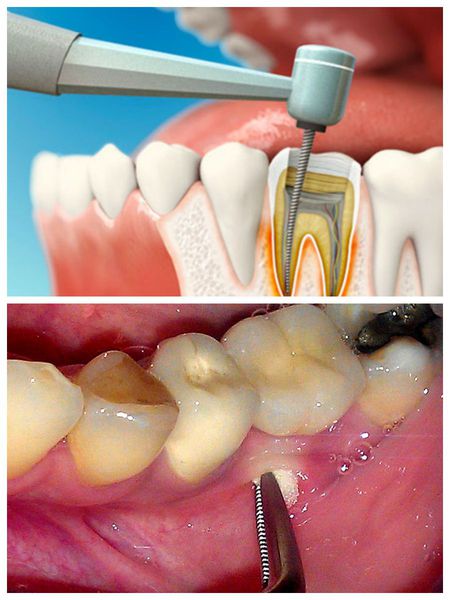

Operacja to podstawowa metoda leczenia ropnia zęba. Jej celem jest usunięcie przyczyny zapalenia (martwej miazgi zęba) oraz odprowadzenie ropy nagromadzonej w miejscu zakażenia. Możliwe są dwa rodzaje zabiegów chirurgicznych:

- Proste leczenie — dostęp do kanału korzeniowego uzyskuje się przez koronę zęba, następnie usuwa się martwą miazgę.

- Złożone leczenie — wykonuje się nacięcie tkanek miękkich i zakłada dren w celu odprowadzenia ropy z miejsca zakażenia.